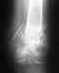

Мне нужна помощ,не знаю куда и к кому обратиться. в детстве была травма на правой руке, тчно описать не могу, возможно перелом или растежение в области указательног пальца. в настоящее время пропала чуствительность укахательного и большого пальца, сильное искревление кисти , трудно брать предметы. Подскажите куда обратиться